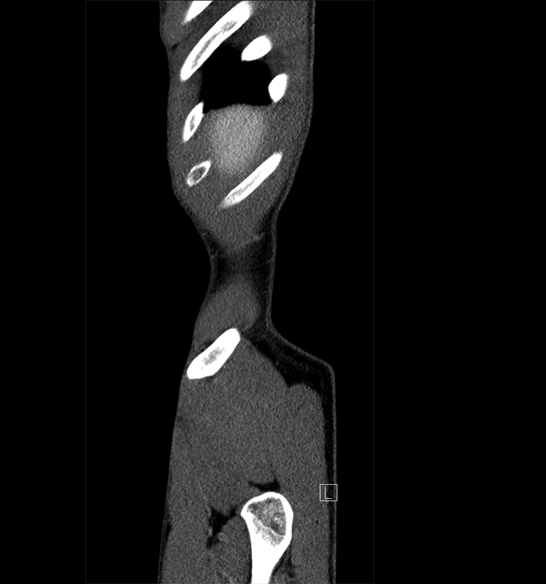

Body

Covers abdominal CT anatomy.